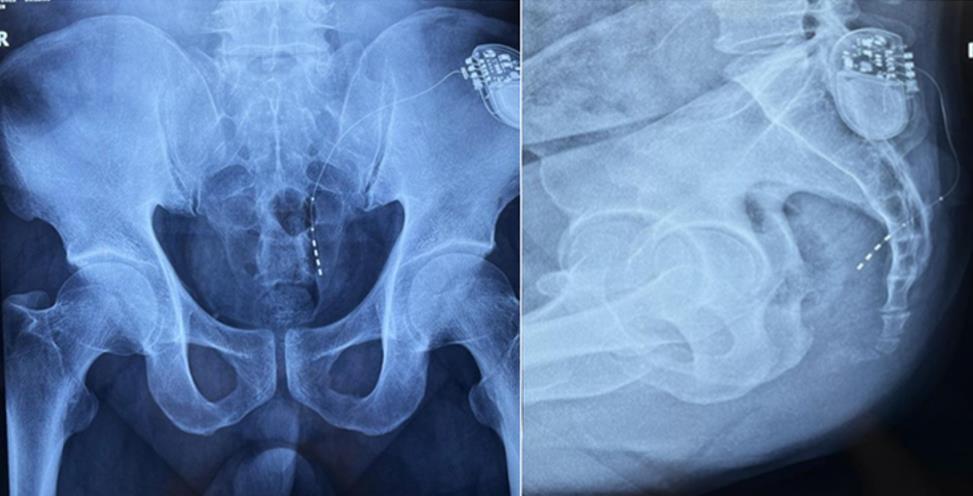

大平板一體式移動C形臂術中影像

? 傳統9英寸的平板探測器或影像增強器C形臂,成像范圍較小,在進行導絲定位觀察時,受手術床的限制無法呈現大視野的透視圖像,需要進行多次的拍攝,降低手術的效率。而普愛醫療大平板一體式移動C形臂裝備一塊30cm x 30cm大平板探測器,超大的成像區域彌補了因擺位不便造成的拍攝困難。

? 相較于影增C形臂,平板探測器成像的畸變更少,能夠準確體現電極和骶孔位置關系,提高手術效果預期。